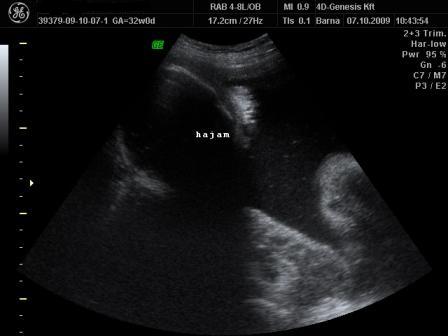

Ma tehát megjártuk a 4D-t meg a cipőboltot. 1,5 órát UHzott a csaj, mert Drága Kistesó nem akarta mutatni magát. Már tornáztam, ettem, ittam épp csak háztömböt nem mentem futni... A végén sikerült 1-2 jobb képet csinálni (azt is csak profilból). Súlya 2 kg (1900valamennyi), mindene 32 hetesnek megfelelő. Minden a helyén van és megvan, hosszú haja van és már most zsíros a Drágám.

No és képek: